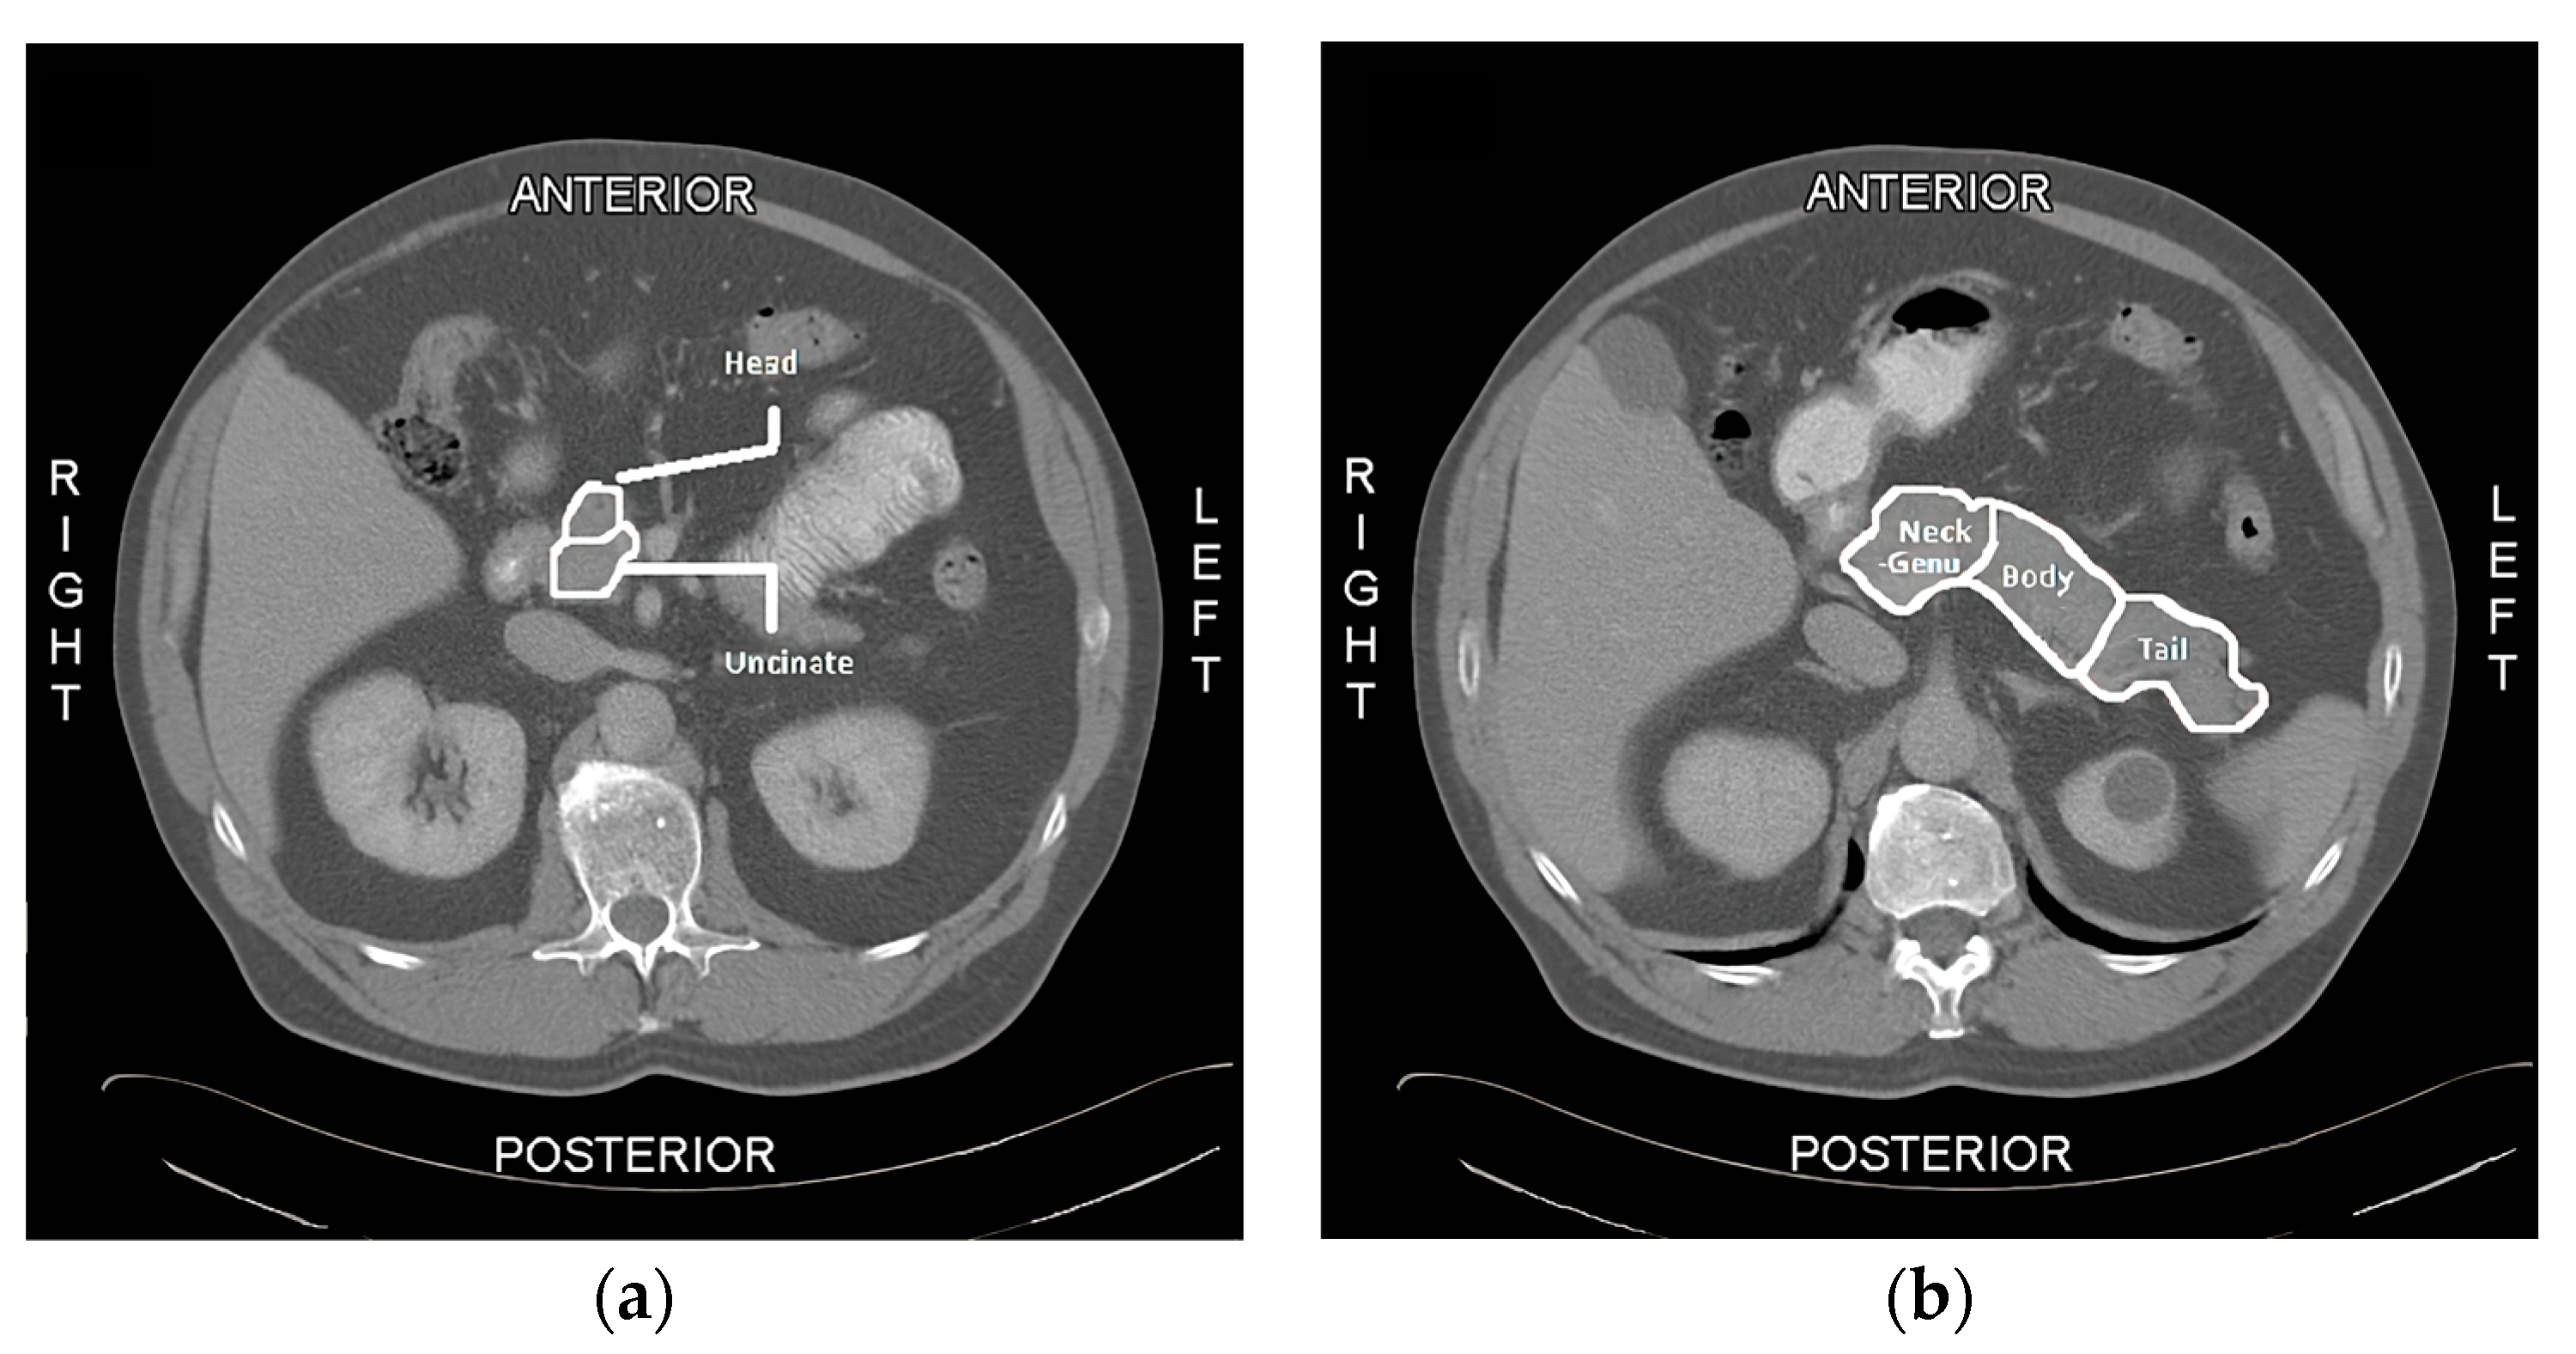

2.1. QTA Analysis of the Pancreas